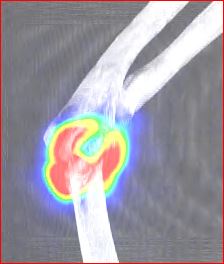

Pacient indikován ortopedem pro scintigraficky (obr.1,2,3) prokázanou synovialitidu pravého loketního kloubu.

/ Obr.2.: SPECT/CT v koronárním řezu - zvýšený krevní pool v oblasti synoviální membrány pravého loketního kloubu.